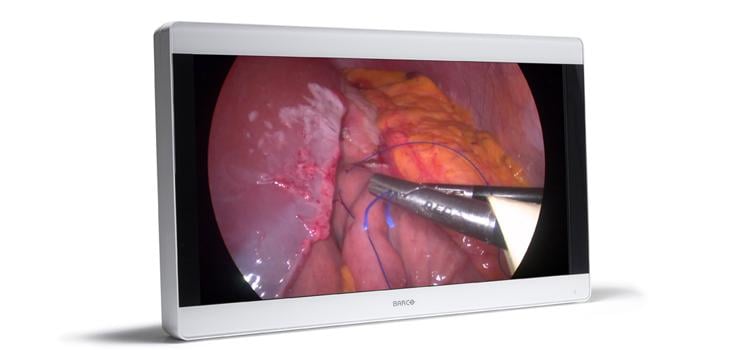

Olympus, a global technology leader in designing and delivering innovative solutions for medical and surgical procedures ...